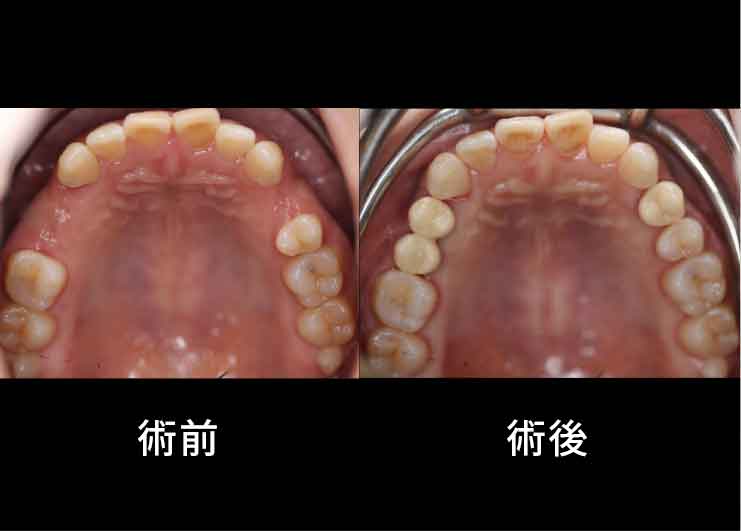

Case1. 21歳女性

生まれつき上あごの3本の歯が欠損しており、骨の幅が少ないケース。

X-ガイド使用により、上あごの上方にある上顎洞を避けた手術を行いました。

CTスキャンを撮影後、DTX Studioによる手術シミュレーションを行い、X-ガイドによるナビゲーション手術を行いました。

CTスキャンを撮影後、DTX Studioによる手術シミュレーションを行い、X-ガイドによるナビゲーション手術を行いました。